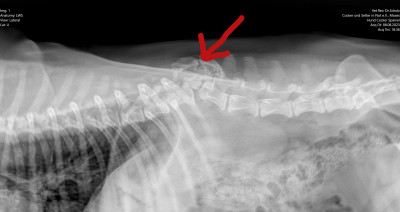

Wir waren mit Moses zur Kontrolle in der Tierklinik

Die "Bruch-"Stelle ist noch weiterzusammengewchsen, so dass der TA meinte, dass "wenn an Moses Rücken noch einmal etwas passieren würde, es an einer anderen Stelle sein würde, weil die Verletzungsstelle inzwischen äußerst stabil ist."

Das ist die vordere hochstehende Stelle, die hintere ist der Beckenknochen.